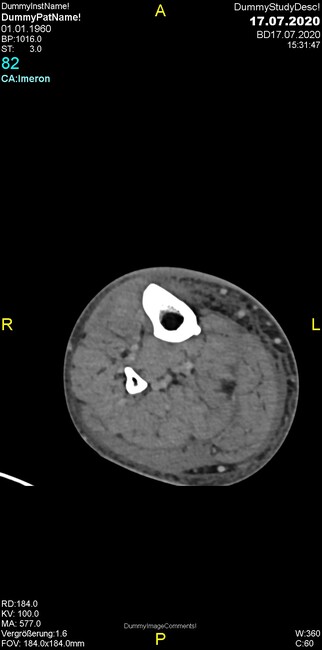

Um welche Modalitäten handelt es sich?

- Röntgen p.a. und lateral, CT coronar Knochenfenster, CT axial Weichgewebsfenster

- Röntgen p.a. und oblique, CT coronar Knochenfenster, CT axial Weichgewebsfenster

- Röntgen p.a. und lateral, CT sagittal Weichgewebsfenster, CT coronar Knochenfenster

- Röntgen p.a. und oblique, CT sagittal Knochenfenster, CT coronar Weichgewebsfenster

- Röntgen p.a. und lateral, CT coronar Weichgewebsfenster, MR axial

Was fällt in der Projektionsradiographie auf?

- Verdichtung im Recessus suprapatellaris

- Aufhellungslinie in Projektion auf die Femurkondylen

- Erhöhter tibialer Slope

- Hypertransparenz tibial

- Subluxationsstellung im Kniegelenk

Was trifft auf den Befund zu?

- Der Befund beschränkt sich auf den Knochen.

- Es besteht hochakuter Handlungsbedarf.

- Der Befund ist tendenziell benigne.

- Der Befund ist tendenziell maligne.

- Der Befund weist einen Zusammenhang zum Patientenalter auf.

Was fällt in der CT im Knochenfenster auf?

- Mediale Gelenkspaltverschmälerung

- Dezente Erosion der fibulären Kortikalis

- Frakturspalt der lateralen Tibiametaphyse

- Weichgewebskalzifikationen lateral angrenzend an den Gelenkspalt

- Osteolyse der Tibiametaphyse unter Beteiligung der Kortikalis